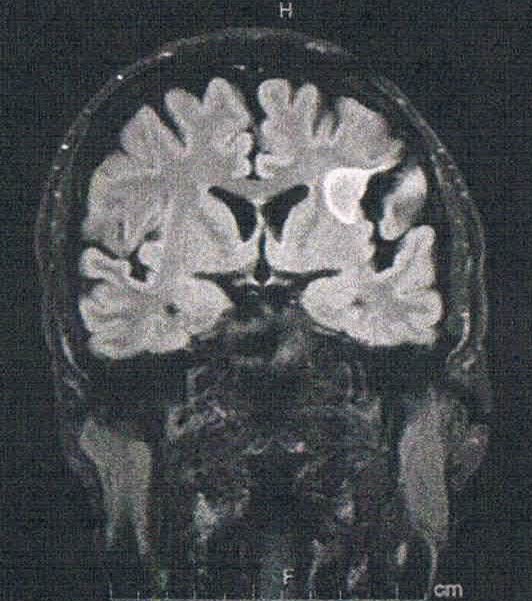

- びまん性星細胞腫グレード2(悪性転化しやすい腫瘍)

- 今回のは白く映って大きく見えるが変化は無し。

- 珍しく前後方向の断面を見せてくれた